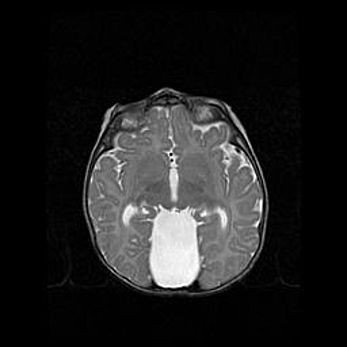

Лейкомаляция с кистозно-глиозной дегенерацией головного мозга.

Возраст: 2 месяца 25 дней

Вес: 6400 г

Окружность головы: 40 см

Срок гестации: 41 неделя

Лейкомаляцию относят к ишемически-гипоксическим повреждениям головного мозга, диагностируемым у новорожденных. При лейкомаляции в головном мозге обнаруживают очаги некроза, возникшие после тяжелой гипоксии и нарушения кровотока. В процессе морфогенеза очаги проходят три стадии: 1) развития некроза, 2) резорбции и 3) формирования глиозного рубца или кисты. Перивентрикулярная лейкомаляция (ПЛ) встречается примерно в 12% случаев среди новорожденных, обычно – у недоношенных детей, причем, частота ее зависит от массы, с которой младенец появился на свет. Наибольшее число малышей страдает лейкомаляцией, если масса при рождении 1500-2500 г.